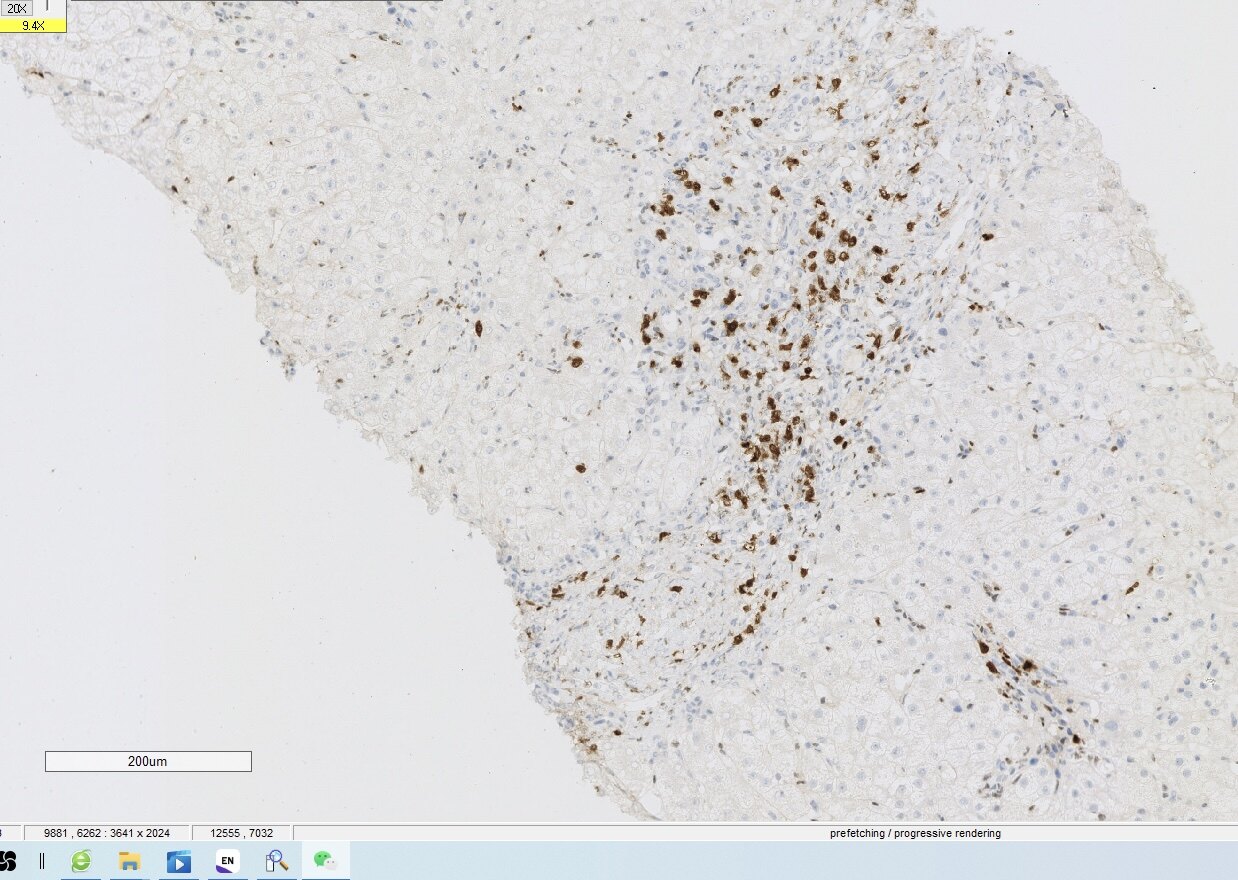

肝活检的意义

经常碰到长期肝功能异常的患者,常规检查做了仍不能找到原因。这时候我会建议进行肝活检,虽然有时候肝活检仍然不能给予一个确切的诊断,但是起码能够知道病变的部位在哪?是肝细胞损伤为主,胆管损伤为主,还是两者兼有,这样我们就能根据不同的患者给予不同的治疗方案,做到精准治疗和个体化治疗!